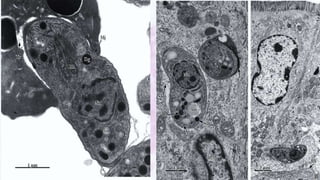

ULTRAESTRUTURA

CULTIVO – TAQUIZOÍTO (in vivo)

Os taquizoítos crescem na cavidade

peritoneal de camundongos, às vezes

produzindo ascite, e também crescem

na maioria dos outros tecidos do

hospedeiro.

Taquizoítos de uma cepa virulenta

podem ser aspirados da cavidade

peritoneal após eutanásia.

• A passagem rápida e frequente de taquizoítos de baixa virulência pode aumentar a virulência.

• Cepas de laboratório antigas não produzem mais oocistos depois que os cistos teciduais são

dados aos gatos.

CULTIVO – TAQUIZOÍTO (in vitro)

• O rendimento de taquizoítos irá variar com a linhagem celular e a cepa

de T. gondii. As cepas “virulentas” de camundongo destroem

rapidamente as células, enquanto as cepas “avirulentas” crescem

lentamente, causando danos celulares mínimos. O tempo médio de

geração dos taquizoítos da cepa RH é de 5 horas.

CULTIVO – CISTOS TECIDUAIS (in vivo)

• Para manutenção de cistos teciduais em

camundongos, esses animais devem ser inoculados

s.c. com homogeneizado de cérebro a cada 3 a 6

meses.

• Os cistos teciduais do T. gondii têm gravidade

específica de 1,056.

CULTIVO – CISTOS TECIDUAIS (in vitro)

• A maioria das cepas de T. gondii

desenvolverá espontaneamente cistos

teciduais em cultura de células sem

manipulação.